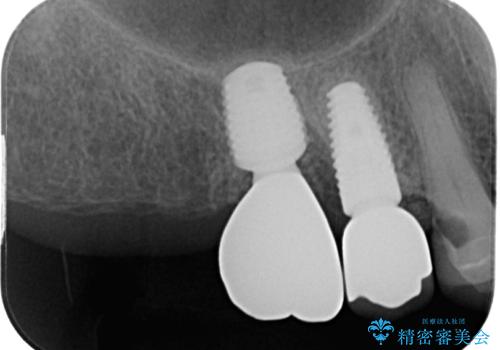

破折して抜歯となった奥歯 抜歯即時埋入・即時荷重インプラントによる補綴治療

歯肉を開いて確認をしたところ、著しく骨欠損しており、目視でも歯根破折が確認されました。

3つある歯根の内、1つのみに骨欠損がある状態で、インプラント埋入に十分な骨の状態でした。

抜歯即時埋入・即時荷重の適応と判断されたため、インプラントによる補綴治療を行うこととしました。

埋入時に十分な安定値が獲得でき、埋入した際に仮歯を装着することができました。

術後の経過は安定しており、抜歯から3ヶ月で治療を終えることができました。